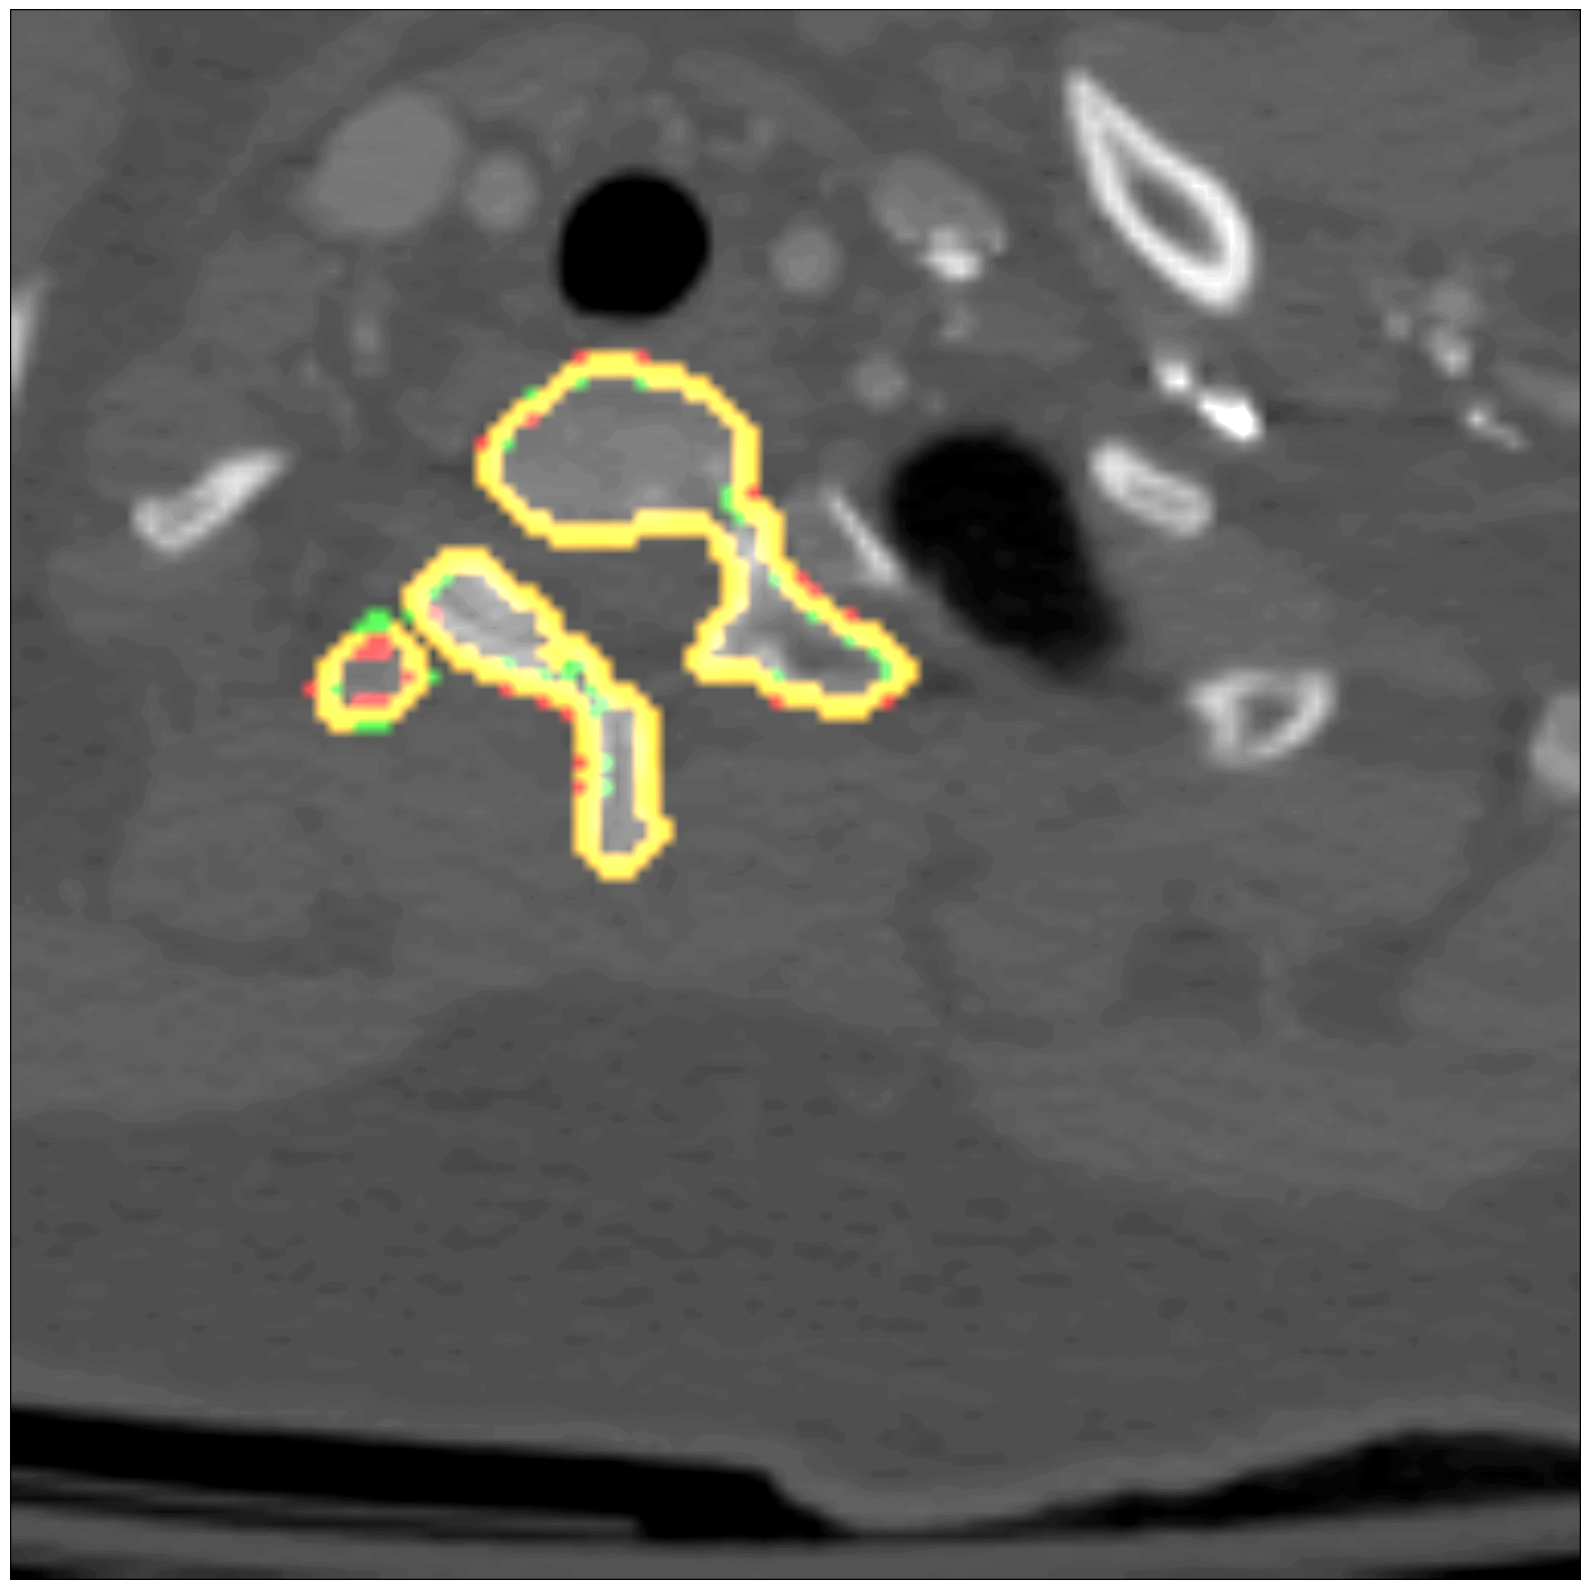

Some segmentation results at different vertebrae (top) and liver (bottom) areas are depicted in Fig. 2. The red contour corresponds to the outline of the prediction, green to the ground-truth and yellow to the overlap of the outlines.